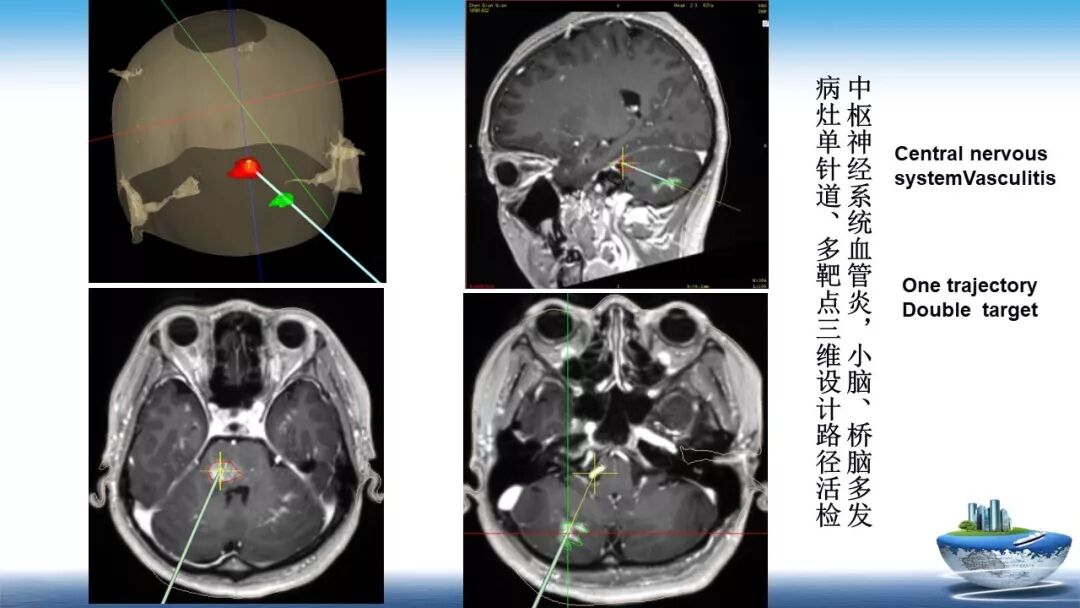

立体定向活检在脑干中线病变精准诊断中的作用

今天为大家带来的是中国人民解放军总医院第六医学中心(原中国人民解放军海军总医院)王亚明、于新、张剑宁带来的精彩课题分享:立体定向活检在脑干中线病变精准诊断中的作用,欢迎观看、阅读!